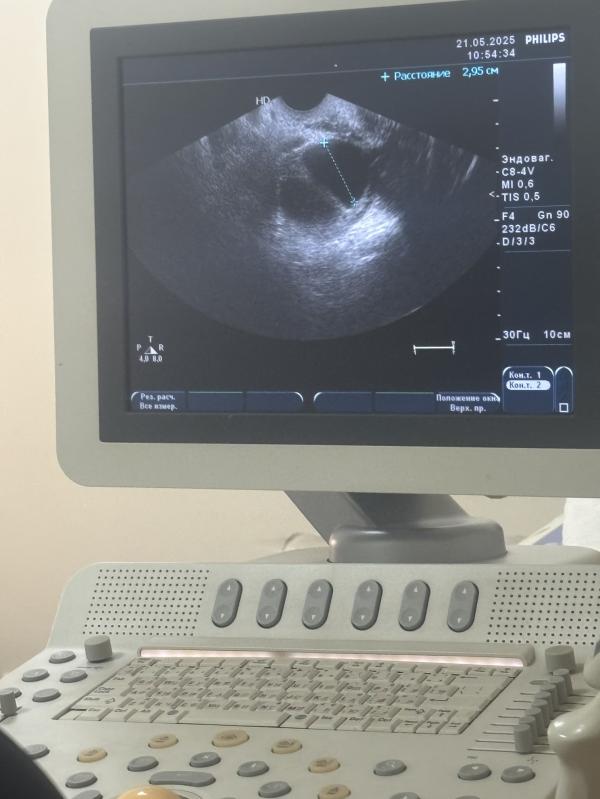

До этого ставили в нем фолликул который не лопнул сейчас когда ждать мес через 2 Нед